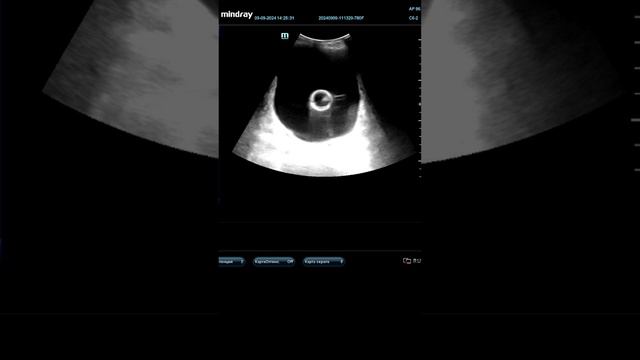

КАТЕТЕР ФОЛЕЯ ДЛЯ РАСКРЫТИЯ ШЕЙКИ МАТКИ | Применение катетера Фолея для стимуляции родов

Акушерство и гинекология — раздел ...

Видео демонстрирует процесс постановки мочевого катетера Фолея у женщины. Детально описывается подготовка, стерильные процедуры, использование перчаток,...